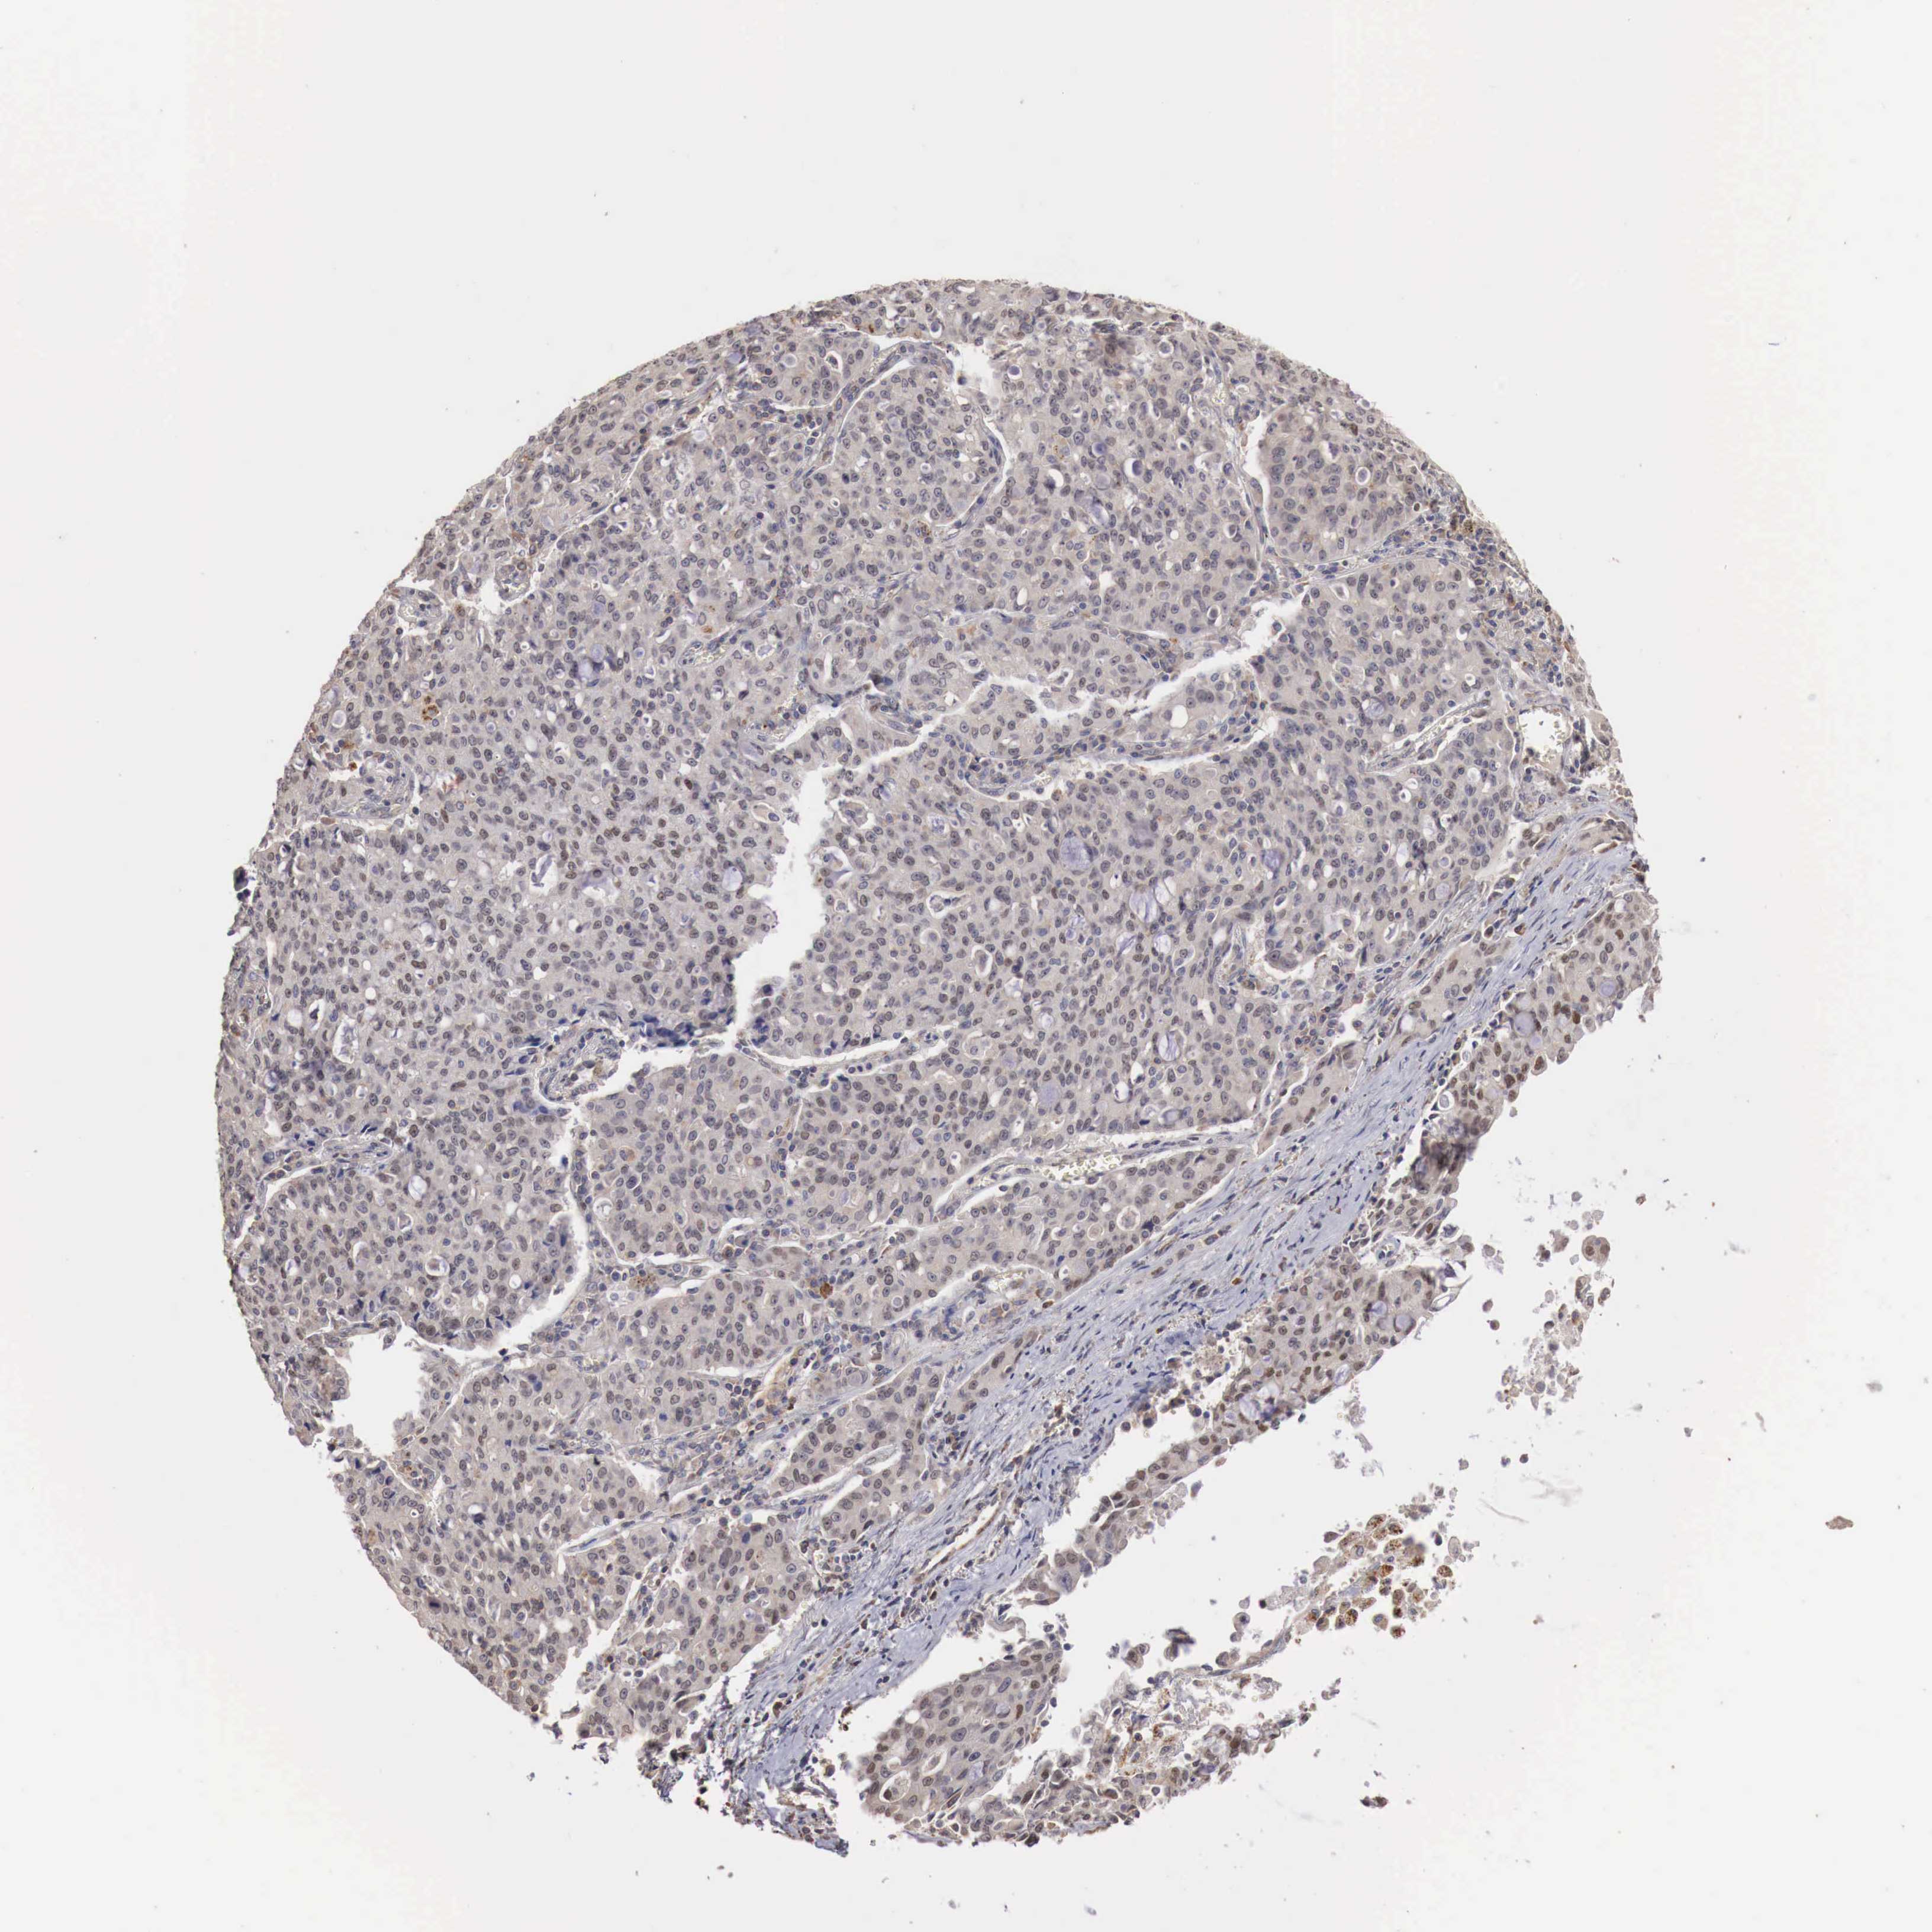

LUNG SQUAMOUS CELL CARCINOMA (TCGA) - Interactive survival scatter ploti

The Survival Scatter plot shows the clinical status (i.e. dead or alive) for all individuals in the patient cohort, based on the same data that underlies the corresponding Kaplan-Meier plots. Patients that are alive at last time for follow-up are shown in blue and patients who have died during the study are shown in red.

The x-axis shows the expression levels (FPKM) of the investigated gene in the tumor tissue at the time of diagnosis. The y-axis shows the follow-up time after diagnosis (years). Both axes are complimented with kernel density curves demonstrating the data density over the axes. The top density plot shows the expression levels (FPKM) distribution among dead (red) and alive patients (blue). The right density plot shows the data density of the survived years of dead patients with high and low expression levels respectively, stratified using the cutoff indicated by the vertical dashed line through the Survival Scatter plot. This cutoff is automatically defined based on the FPKM cutoff that minimizes the p-score. The cutoff can be changed by dragging the vertical line or by entering a cutoff value in the square labeled "Current cut-off".

Under the Survival Scatter plot the p-score landscape (black curve; left axis) is shown together with dead median separation (red curve; right axis). Dead median separation is the difference in median mRNA expression between patients who have died with high and low expression, respectively. It is calculated as follows: median FPKM expression of dead patients with high expression - median FPKM expression of dead patients with low expression. This is intended to aid the user in visually exploring custom cutoffs and the associated p-scores and dead median separation.

Individual patient data is displayed and can be filtered by clicking on one or more of the category buttons on the top of the page. Categories describing expression level and patient information include: high, low, alive, dead, female, male and tumor stages. The scale of the x-axis can be toggled between linear and log-scale by clicking on the "x log" button. Mouse-over function shows TCGA ID, patient information and mRNA expression (FPKM) for each patient.

& Survival analysisi

Kaplan-Meier plots summarize results from analysis of correlation between mRNA expression level and patient survival. Patients were divided based on level of expression into one of the two groups "low" (under cut off) or "high" (over cut off). X-axis shows time for survival (years) and y-axis shows the probability of survival, where 1.0 corresponds to 100 percent.

KHDRBS3 is not prognostic in Lung Squamous Cell Carcinoma (TCGA)

: 2.35

P scorei

N/A

Average pTPM 8.8

Number of samples 489